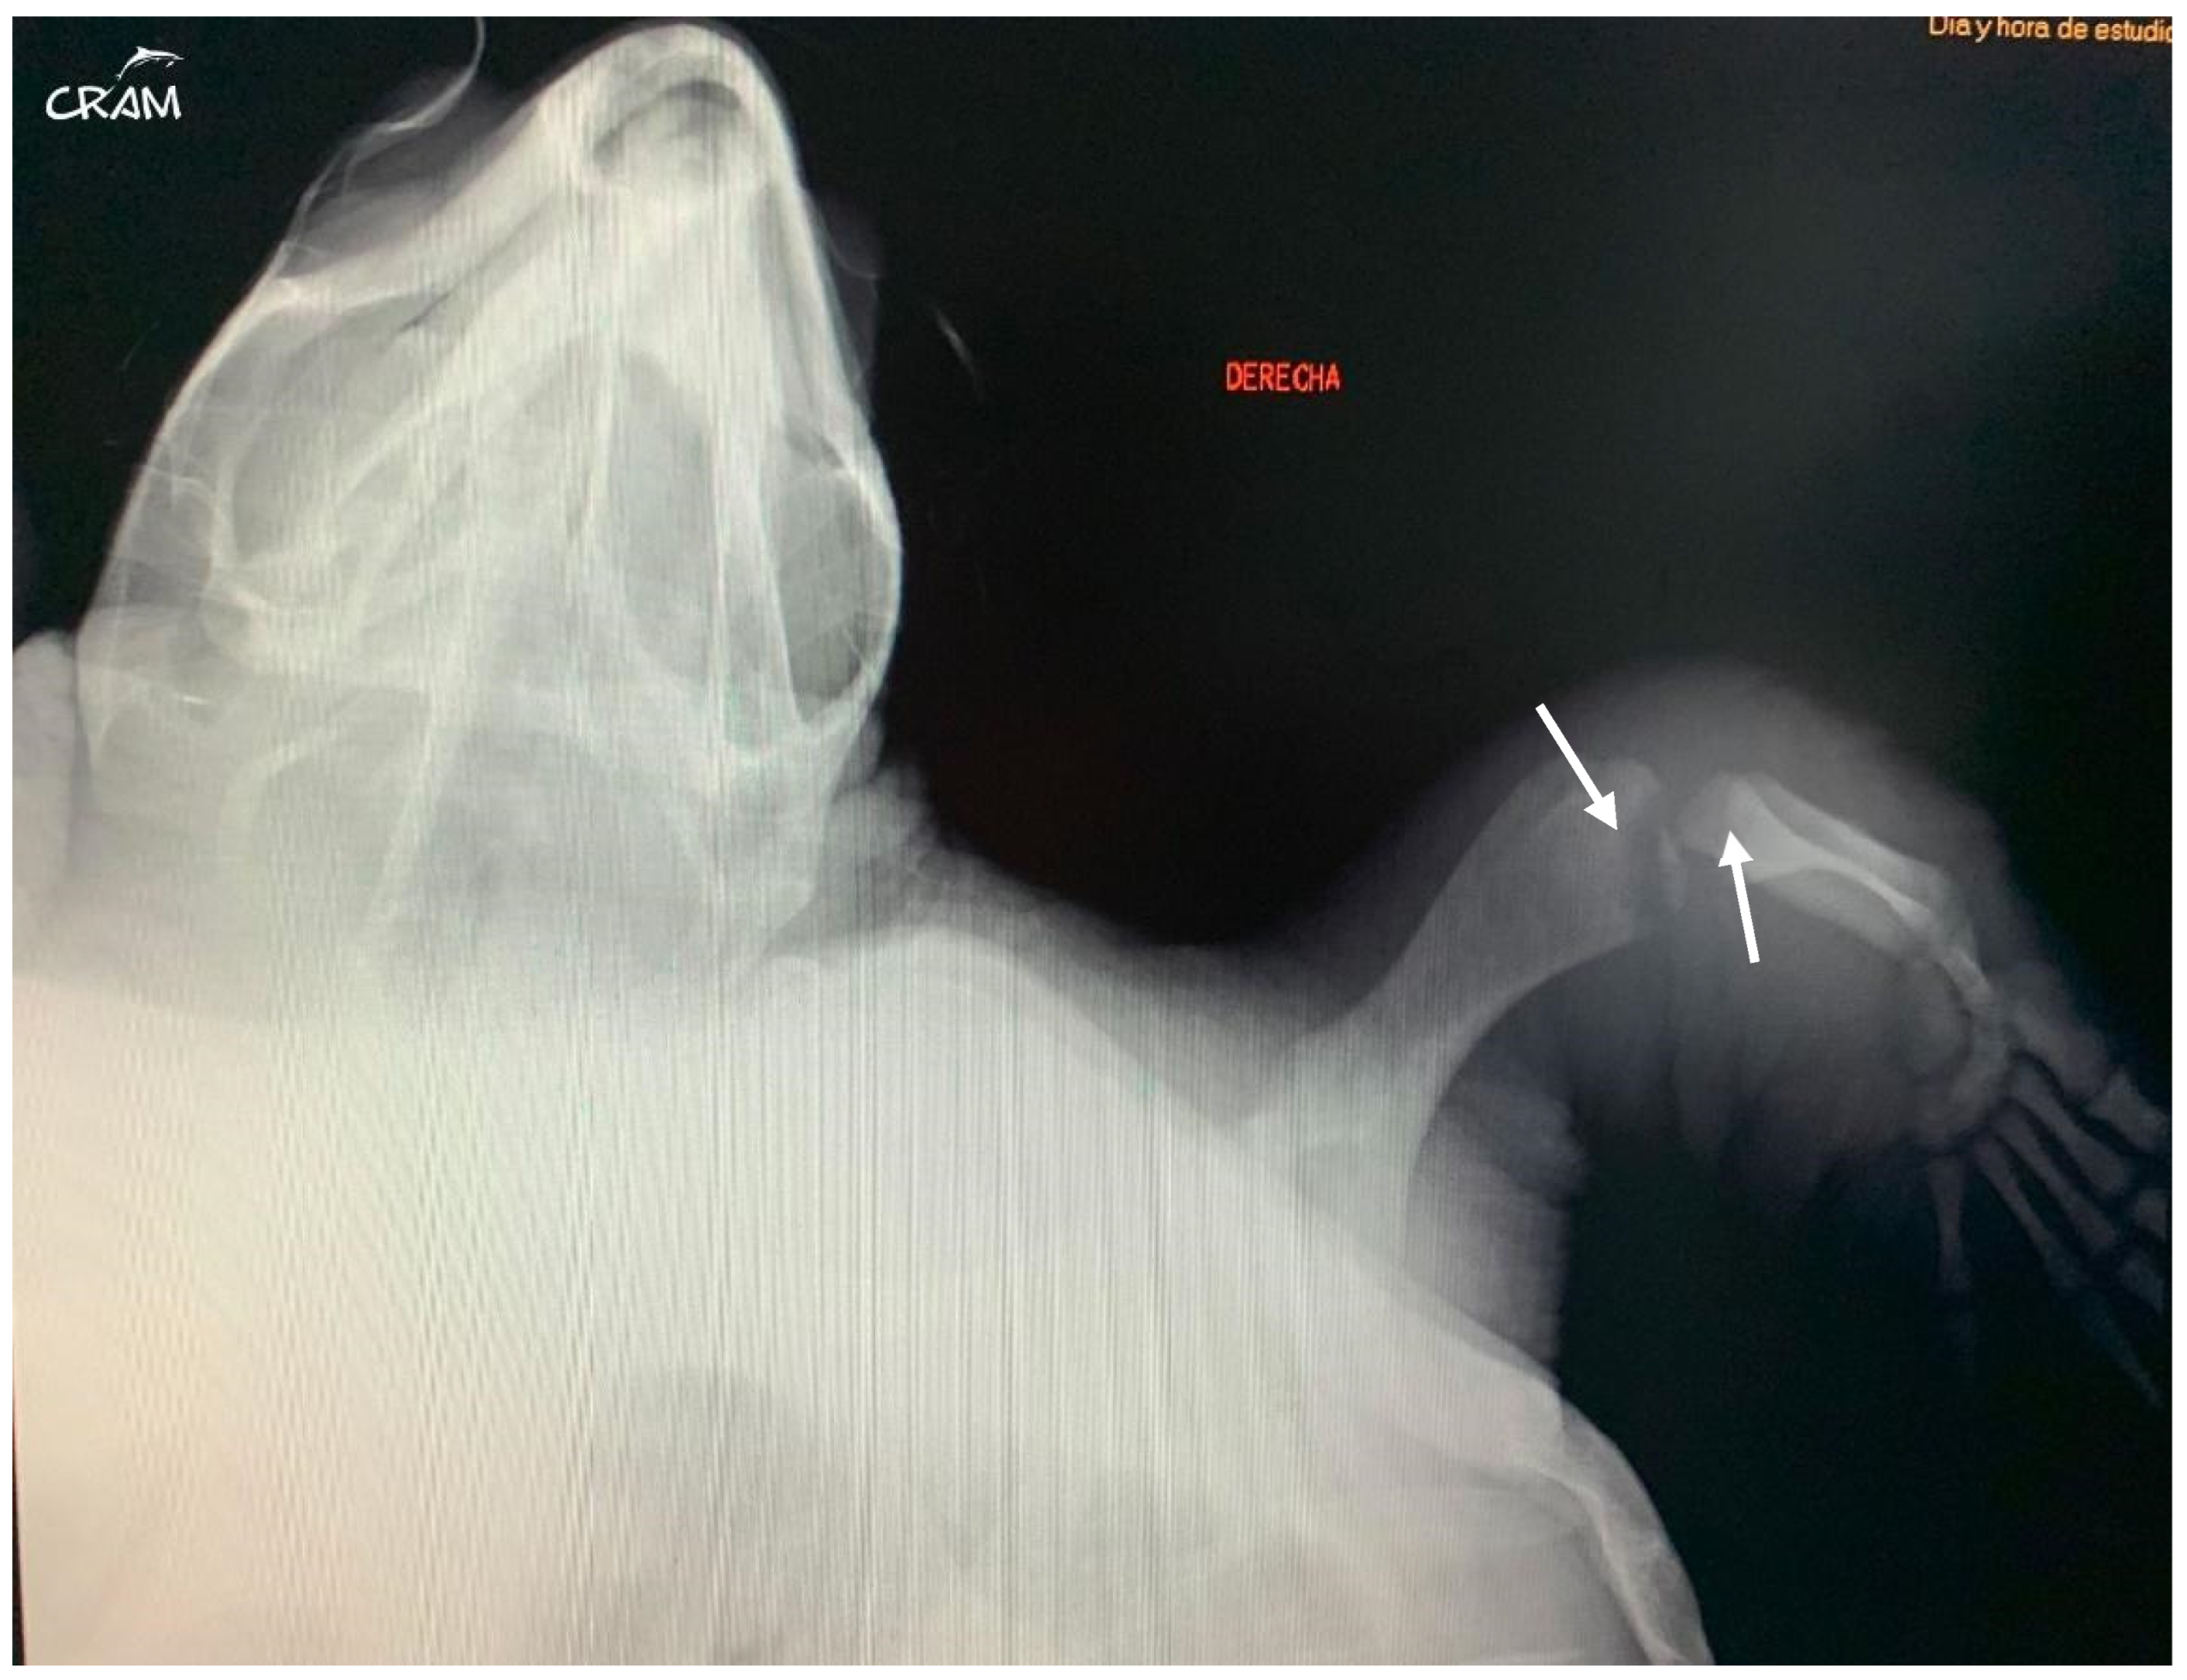

Visible swelling and lameness of the right fore and hind flippers were first noted around day 45 of rehabilitation (Figure 4). The turtle had reduced use and range of motion of the affected limbs. Palpation of right elbow and right knee elicited a pain response. Both joints presented increased periarticular soft tissue. A radiographic study of the turtle was performed and showed poorly defined osteolytic process restricted to the distal end of the humerus and femur and the proximal end of the radius and tibia. In the case of DON, changes in imaging are seen early at 4 months after hyperbaric exposure and can be seen as late as 8 months to more than a year [6]. Radiographic studies were repeated every 10–14 days to evaluate the progression of the lesions.

Hard edema with increased periarticular soft tissue and pain was noticed at palpation during clinical evaluation in veterinary medicine [21]. At the beginning of signs, radiographic lesions were polyostotic and poorly defined (Figure 5 and Figure 6).

Figure 6. Right pelvic girdle in dorso-ventral view at day 45 of rehabilitation. Visible bone lysis on the distal end of the right femur (arrow).